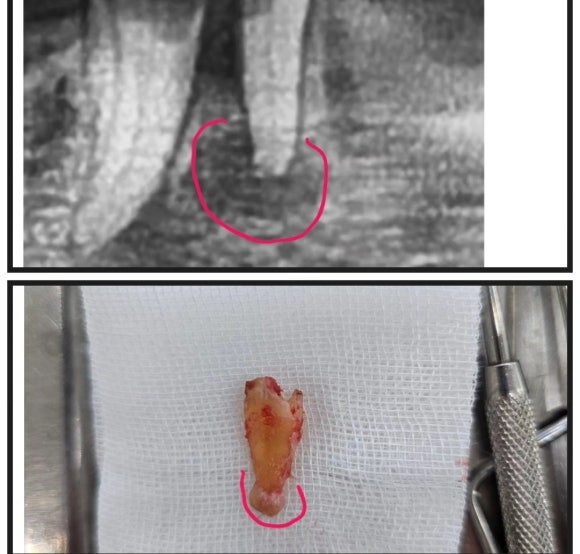

치근단 농양으로 인해 발치를 한 치아

치아를 발치를 하고 나면,

뼈가 녹아내려 사진 상으로 검게 보이는 부분이 빈 공간이 아니고

염증 조직으로 가득 차서 세균들이 공격적으로 뼈를 녹여 내리고 있습니다.